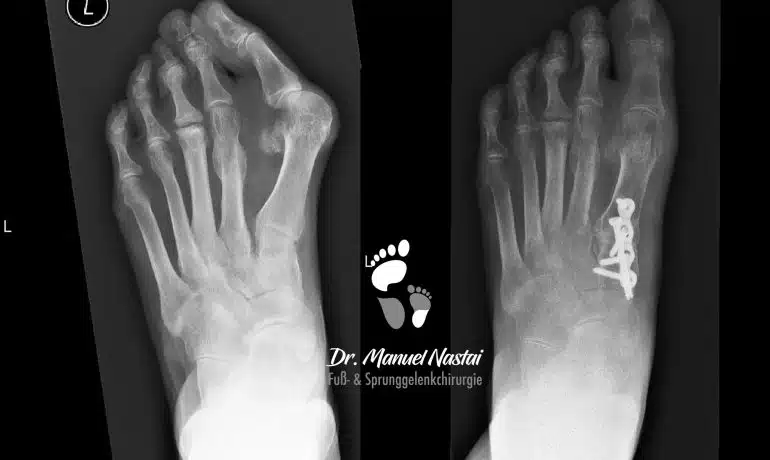

Lapidus-Arthrodese mit plantarer Platte

Die Lapidus-Arthrodese ist eine operative Methode zur Korrektur der Hallux valgus Fehlstellung. Dies ist eine Technik mit dem größten Korrekturpotenzial und wird bei extremen Ausprägungen...